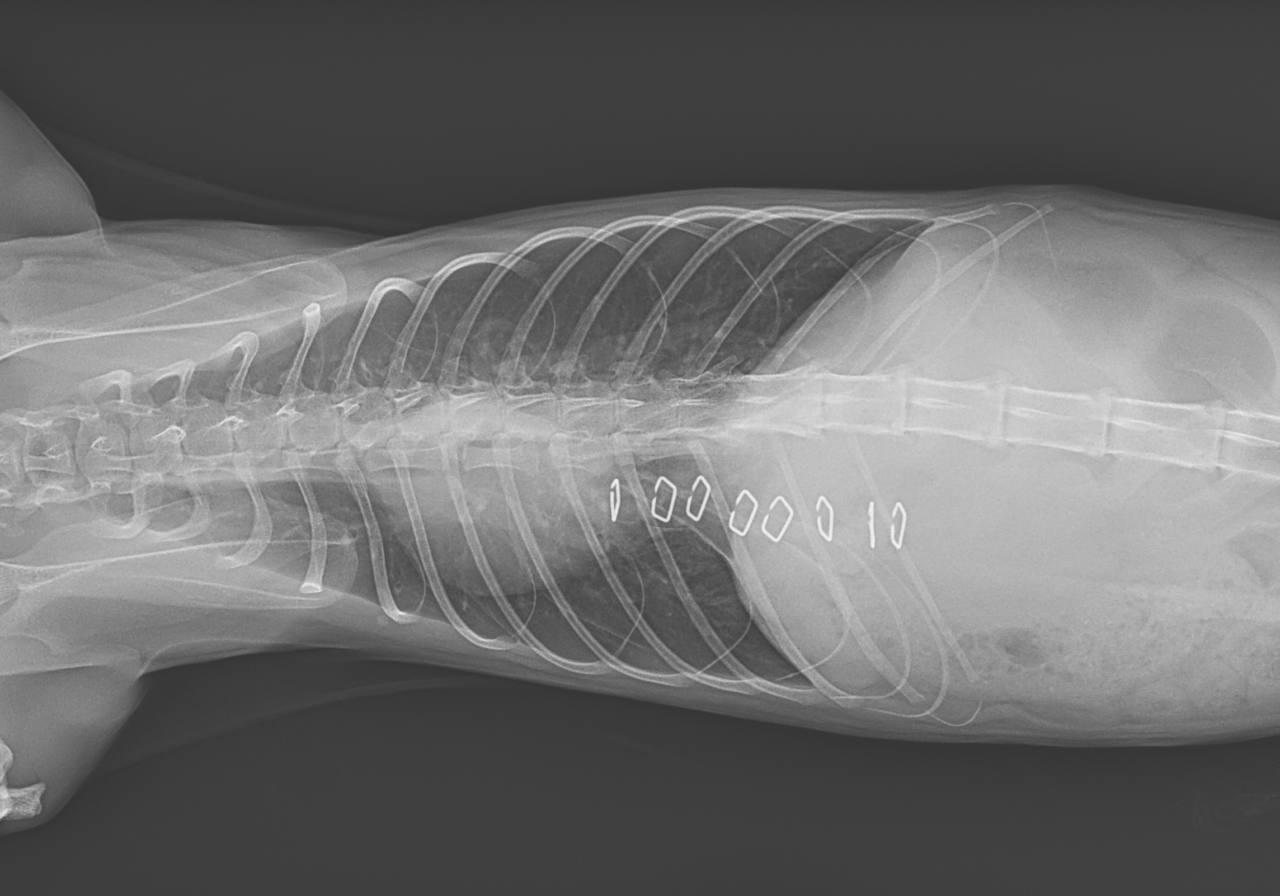

保護した猫さんの呼吸が早いかも??? かかりつけの先生に相談されたようです。エックス線検査で横隔膜ヘルニアが確定されました。外科的な対応を希望され来院されました。肝臓のほとんどが胸腔内にヘルニア(逸脱)しており、開腹アプローチで横隔膜を整復しました。正しい位置に臓器が戻ったので、これからは呼吸が楽になります。